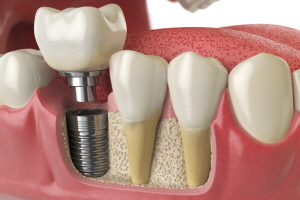

임플란트는 크게 세 가지 구성 요소로 나뉩니다.

- 보철물: 실제 치아 역할을 하는 인공 치아 부분입니다.

- 지대주: 보철물과 픽스쳐를 연결하는 부분으로, 잇몸에 위치하게 됩니다.

- 픽스쳐(고정체): 임플란트의 뿌리 역할을 하며, 잇몸뼈에 고정됩니다.

각 부위에 어떤 재료가 사용되느냐에 따라 가격이 달라집니다. 예를 들어, 보철물은 금속 또는 세라믹으로 만들 수 있고, 픽스쳐는 티타늄 또는 지르코니아 같은 재료를 사용할 수 있습니다.